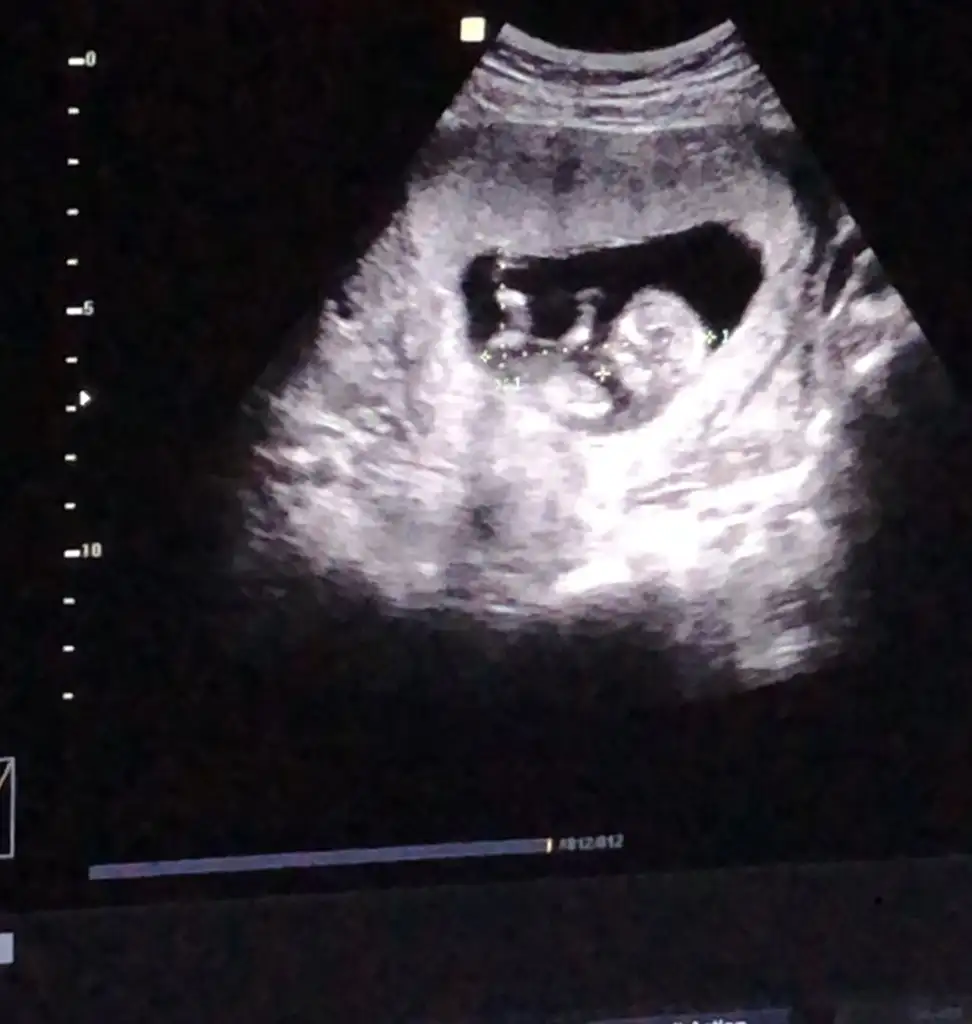

dr soylemeden siz gorun genital nub teorisi ( bebegin cinsiyeti)

Merhaba kızlar daha öncede ultrason görüntüsü paylaşmıştık fakat pek net olmadığı için yorum yapamamıştınız.Rica etsem yine bakabilir misiniz? Şimdiden teşekkürler🤗